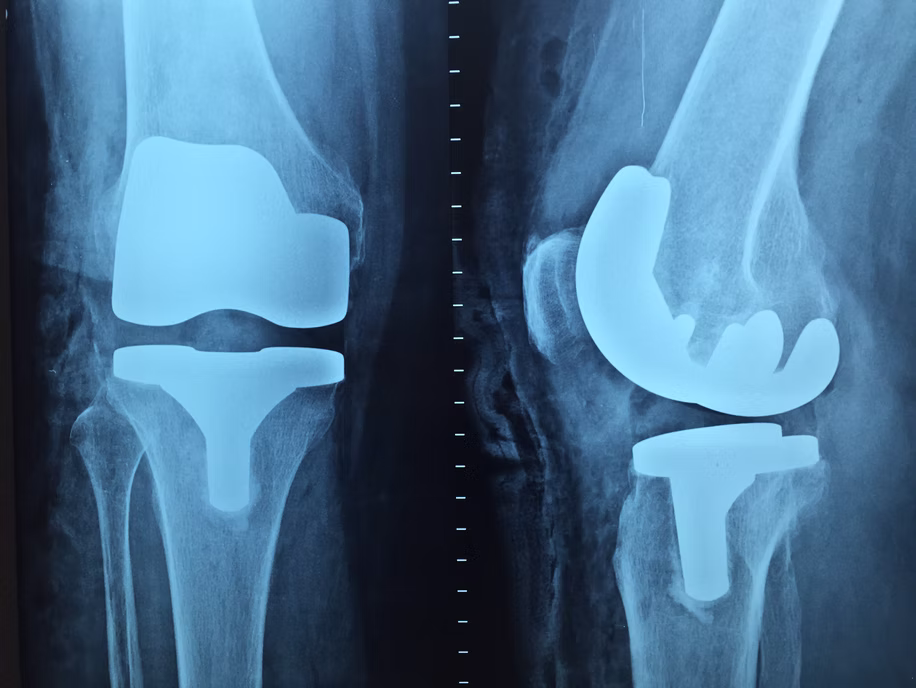

تُعرف أيضًا باسم استبدال مفصل الركبة الكامل، وهي عملية جراحية تهدف إلى علاج الألم وصعوبة الحركة في مفصل الركبة. يُوصى بها للمرضى الذين يعانون من خشونة المفاصل (الفُصال العظمي)، أو تمزق الغضروف الهلالي، أو تلف الغضاريف، أو الأمراض التنكسية في المفصل.